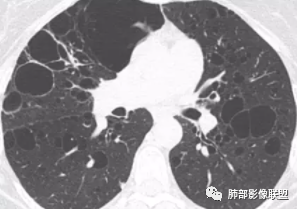

晨读:双肺多发大小不等囊腔影,部分囊有融合,形态不规则,部分壁偏薄,部分囊壁偏厚,囊壁可见结节?血管?右肺上叶及左肺下叶可见条状高密度影,双侧胸膜结节样增厚,临床年轻女性,考虑LAM,鉴别LIP

晨读:女,31,间断咳嗽咳痰9个月,双肺多发大小不等囊泡影,壁薄厚不均,部分囊泡融合成片,双肺另见结节影,边界清晰,考虑PLCH,LAM。

晨读,青年女性,双肺及胸膜下多发大小不等囊腔,大部分呈薄壁,部分囊壁略厚,边缘毛糙,部分囊腔有融合,双肺内散在条状高密度影,考虑LAM

晨读:女,31,间断咳嗽、咳痰9月。卵巢交界性囊腺瘤术后。胸部CT:双肺多发大小不等薄壁囊腔影,部分融合,形态不规则,个别囊壁偏厚。右肺上叶及左肺下叶纤维索条影。左下叶不规则囊腔影,壁不均匀增厚,周围不规则实性成分加GGO,放射性毛刺,胸膜牵拉。考虑:囊腔型Ca?转移?鉴别PLCH,Lam,LIp,BHD,CF,CPAM等,听大咖解析。

胸部CT:两肺多发囊腔,中上肺受累为主,囊腔形态不规则(囊有点丑),分叶状,囊壁厚薄不均,大部分囊壁薄。尚有一些结节影。